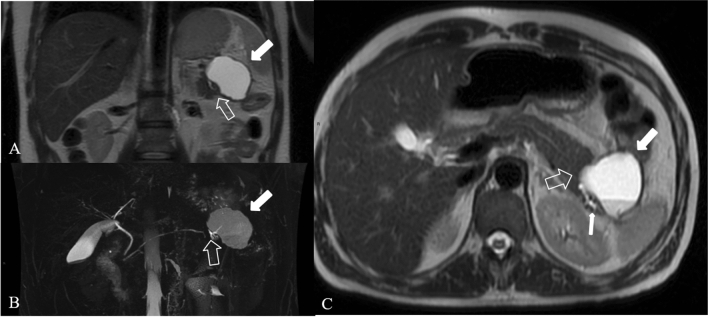

The severe necrotic pancreatitis with pancreatic duct disruption, called disconnected pancreatic duct syndrome (DPDS) (Fig. 14), has 10% to 31% as prevalence [33]. In these cases, the combination of MRI and MRCP provides a noninvasive method showing not only the pancreas and peripancreatic changes but also analyzing the proximal and distal ends of the ruptured main pancreatic duct and possible fistula. Therefore, the use of MRI and MRCP is more advantageous to evaluate the main disconnected pancreatic duct syndrome caused by acute necrotizing pancreatitis [34]. As the severity increases, the incidence of pancreatic duct rupture also increases. The diagnosis of pancreatic duct disruption should be considered if there is a peripancreatic necrosis area at least 2 cm, and MRCP shows that the main pancreatic duct of the upstream pancreatic tissue travels to the WON area of the intra and/or extra pancreatic tissue. MRCP performed with secretin is emerging as the imaging study of choice for the diagnosis of a disconnected pancreatic duct, which demonstrates a cutoff of the downstream pancreatic duct with enhancing upstream pancreatic parenchyma [35]; S-MRCP may on occasion shows the passage of exocrine output into the collection.

Fig. 14.

Disconnected pancreatic duct syndrome in a 41 years-old man. Coronal (a), axial (c) T2 weighted MR images and MRCP (b) 3 weeks after the onset of the symptoms show focal interruption of the Wirsung duct (empty arrow)—upstream pancreatic duct dilatation (thin arrow in c)—and a heterogeneous encapsulated fluid collection in the pancreatic tail (white arrow)